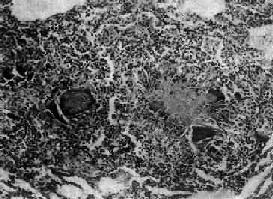

第一节 结核病结核病(tuberculosis)是由结核杆菌引起的一种慢性传染病。全身各器官均可发生,但以肺结核最为多见。其病变特征是结核结节形成并伴有不同程度的干酪样坏死。 【病因和发病机制】 结核病的病原菌是结核杆菌,对人致病的主要类型为人型和牛型。结核杆菌含有脂质、蛋白和多糖类三种成分:①脂质:特别是脂质中的糖脂更为重要。糖脂的衍生物之一称索状因子(cord factor),能使结核杆菌在培养基上生长时呈蜿蜒索状排列。这种形式生长的结核杆菌在动物体内具有毒力。另一种糖脂为蜡质D(wax D),将其与结核菌体蛋白一起注入动物体内,能引起强烈的变态反应,造成机体的损伤。此外,磷脂还能使炎症灶中的巨噬细胞转变为类上皮细胞,从而形成结核结节。脂质除可能与毒力有关外,还可保护菌体不易被巨噬细胞消化。②蛋白:具有抗原性,与蜡质D结合后能使机体发生变态反应,引起组织坏死和全身中毒症状,并在形成结核结节中发挥一定的作用。③多糖类:可引起局部中性粒细胞浸润,并可作为半抗原参与免疫反应。 结核病主要经呼吸道传染。肺结核(主要是空洞型肺结核)病人在谈话、咳嗽和喷嚏时,从呼吸道排出大量带菌微滴(每个微滴可含10~20个细菌)。吸进这些带菌的微滴即可造成感染。少数病人可因食入带菌的食物经消化道感染。细菌经皮肤伤口感染者极少见。 结核病的发生和发展取决于很多因素,其中最重要的是感染的菌量及其毒力的大小和机体的反应性(免疫反应或变态反应)。后者在结核病的发病学上起着特别重要的作用。 目前一般认为,结核病的免疫反应以细胞免疫为主,即T细胞起主要作用。它在受到结核菌的抗原刺激后可转化为致敏的淋巴细胞。当再次与结核杆菌相遇时,致敏的淋巴细胞可很快分裂、增殖,并释放出各种淋巴因子,如巨噬细胞趋化因子、集聚因子、移动抑制因子和激活因子等。这些因子可使巨噬细胞移向结核杆菌,并聚集于该处不再移动,这样就能把结核杆菌限制在局部不致扩散。同时还激活了巨噬细胞,使巨噬细胞体积增大,伪足形成活跃,溶酶体含量增加,细胞内pH下降等。这些改变有助于使吞入的细菌更易被水解、消化和杀灭。此外,激活后的T细胞还可释放其他淋巴因子,加强这一免疫反应,如结核杆菌的生长抑制因子能通过巨噬细胞特异性地抑制细胞内结核杆菌的繁殖而获得免疫。结核结节的形成就是上述各种反应的具体形态学表现。 结核病时发生的变态反应属于IV型(迟发性)变态反应。结核菌素试验就是这种反应的表现,本质上亦为细胞免疫反应。 结核病免疫反应和变态反应常同时发生并相伴出现,但两者关系如何及其对结核病的发生、发展有何影响等问题,长期来尚未解决。在结核病的诊断方面,基因诊断作为结核菌的非培养诊断技术是近年来结核病快速诊断的一项重大突破。它乃借分析结核菌的遗传物质核酸而特异,敏感、快速地检测和鉴定结核杆菌。目前用于结核菌检测和鉴定的基因诊断方法有基因探针技术、染色体指纹技术和PCR技术。 【结核病的基本病变】 结核杆菌在机体内引起的病变属于特殊性炎症,虽其病变具有一般炎症的渗出、坏死和增生三种基本变化,但有其特异性。由于机体的反应性(免疫反应和变态反应)、菌量及毒力和组织特性的不同,可出现以下不同的病变类型: 1.渗出为主的病变 出现在结核性炎症的早期或机体免疫力低下,菌量多、毒力强,或变态反应较强时,表现为浆液性或浆液纤维素性炎。早期病灶内有中性粒细胞浸润,但很快被巨噬细胞取代。在渗出液和巨噬细胞内易查见结核杆菌。此型变化好发于肺、浆膜、滑膜和脑膜等处,说明与组织结构特性亦有一定的关系。渗出性变化可完全吸收不留痕迹,或转变为以增生为主或以坏死为主的病变。 2.增生为主的变化 当菌量较少,毒力较低或人体免疫反应较强时,则发生以增生为主的变化,形成具有一定诊断特征的结核结节(结核性肉芽肿)。单个结核结节肉眼不易看见,三、四个结节融合成较大结节时才能见到。其境界分明,约粟粒大小,呈灰白半透明状,有干酪样坏死时则略呈黄色,可微隆起于器官表面。 结核结节(tubercle)是在细胞免疫基础上形成的,由类上皮细胞(epithelioid cell)、Langhans巨细胞加上外围局部集聚的淋巴细胞和少量反应性增生的纤维母细胞构成。当有较强的变态反应发生时,结核结节中便出现干酪样坏死。巨噬细胞体积增大逐渐转变为类上皮细胞,呈梭形或多角形,胞浆丰富,染淡伊红色,境界不清。核呈圆或卵圆形,染色质甚少,甚至可呈空泡状,核内可有1~2个核仁。多数类上皮细胞互相融合乃形成Langhans巨细胞,为一种多核巨细胞,体积很大,直径可达300μm,胞浆丰富,核与类上皮细胞核的形态大致相同,核数由十几个到几十个不等,有超过百个者。核排列在胞浆的周围呈花环状、马蹄形或密集在胞体的一端(图18-1)。

图18-1 结核性肉芽肿 结节中央为干酪样坏死,周围绕有类上皮细胞、Langhans巨细胞以及淋巴细胞等 3.坏死为主的变化 在结核杆菌数量多、毒力强,机体抵抗力低或变态反应强烈的情况下,上述渗出性和增生性病变均可继发干酪样坏死。病变一开始便呈现干酪样坏死者十分少见。由于坏死组织含脂质较多(脂质来自破坏的结核杆菌和脂肪变性的单核细胞)而呈淡黄色,均匀细腻,质地较实,状似奶酪,故称干酪样坏死。镜下见为红染无结构的颗粒状物。干酪样坏死的形态特点,特别是肉眼所见对结核病的病理诊断具有一定的意义。干酪样坏死物中大都含有一定量的结核杆菌。 干酪样坏死灶内含有多量抑制酶活性的物质,故坏死物可不发生自溶、排出,也不易被吸收。但有时也能发生软化和液化,形成半流体物质。随着液化,结核杆菌大量繁殖,更进一步促进液化的发生。液化固有利于干酪样坏死物的排出,但更重要的是可成为结核菌在体内蔓延扩散的来源,是结核病恶化进展的原因。 以上渗出、增生和坏死三种变化往往同时存在而以某一种改变为主,而且可互相转化。例如渗出性病变可因适当治疗或机体免疫力增强而转化为增生性病变;反之,在机体免疫力下降或处于较强的变态反应状态时,原来的增生性病变则可转变为渗出性、坏死性病变,或原来的渗出性病变转化为坏死性病变。因此,在同一器官或不同器官中的结核病变是复杂多变的。 【结核病基本病变的转化规律】 结核病变的发展和结局取决于机体抵抗力和结核菌致病力之间的矛盾关系。当人体抵抗力增强时,细菌逐渐被控制而消灭,结核病变转向愈复;反之,则转向恶化。 1.转向愈复 主要表现为病变的吸收消散、纤维化、纤维包裹和钙化。 (1)吸收消散:为渗出性病变的主要愈复方式。渗出物逐渐通过淋巴道吸收,病灶缩小或完全吸收消散。较小的干酪样坏死灶和增生性病变如治疗得当也可被吸收。 (2)纤维化、纤维包裹及钙化:增生性结核结节转向愈复时,其中的类上皮细胞逐渐萎缩,结节周围的增生纤维母细胞长入结核结节形成纤维组织,使结节纤维化。未被完全吸收的渗出性病变也可通过机化而发生纤维化。小的干酪样坏死灶(1~2mm)可完全纤维化;较大者难以完全纤维化而由坏死灶周围的纤维组织增生,将干酪样坏死物质加以包裹,以后干酪样坏死逐渐干燥浓缩,并有钙质沉着而发生钙化。 病灶发生纤维化后,一般已无结核杆菌存活,可谓完全痊愈。在被包裹、钙化的干酪样坏死灶中仍有少量细菌存活,病变只处于相对静止状态(临床痊愈),当机体抵抗力下降时病变可复燃进展。 2.转向恶化 主要表现为病灶扩大和溶解播散。 (1)病灶扩大:病变恶化进展时,在病灶周围出现渗出性病变(病灶周围炎),其范围不断扩大,并继而发生干酪样坏死。坏死区又随渗出性病变的扩延而增大。 (2)溶解播散:干酪样坏死物发生溶解液化后,可经体内的自然管道(如支气管、输尿管等)排出,致局部形成空洞。空洞内液化的干酪样坏死物中含有大量结核杆菌,可通过自然管道播散到其他部位,引起新的病灶。如肺结核性空洞通过支气管播散可在同侧或对侧肺内形成多数新的以渗出、坏死为主的结核病灶。此外,结核杆菌还可通过淋巴道蔓延到淋巴结,经血道播散至全身,在各器官内形成多数结核病灶。